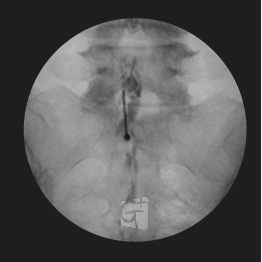

요추 경막외 신경치료

요추 4/5번 경막외 공간에 약물을 주입,

신경줄기로 잘 퍼지는 모습